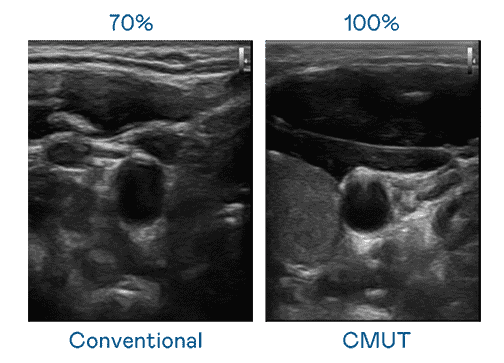

CMUT 技术是一种用电容式微机电元件来产生超音波讯号的技术。。。。与传统 PZT 压电式技术相比,,,,CMUT 频宽增加 30%,,更宽频的超音波讯号让影像解析度大幅提升,,,是实现高影像品质医疗超音波扫描、、促进精准医疗发展的关键技术。。。。

大频宽带来超清晰影像

超音波影像的解析度高低,,,首先取决于探头能发出的讯号频宽。。。。尊时凯龙 CMUT 可提供高清晰的超音波讯号,,,提供高频宽、、、、高灵敏度、、、影像纹理细节更高的超音波影像,,,协助医护人员缩短影像判读时间及利用精准的医疗影像进行诊断。。